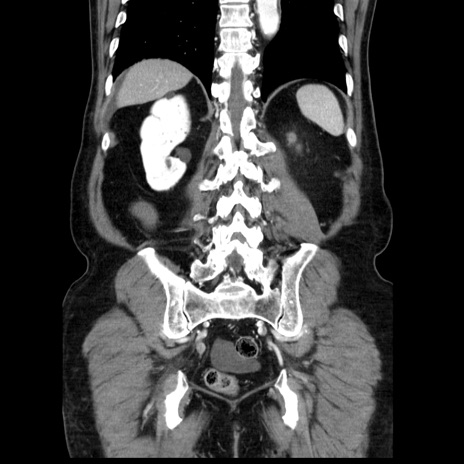

症例30(冠状断像)

【症例】80歳代男性

【主訴】臍周囲痛

【現病歴】約6時間前から臍下部痛が出現。次第に腹部膨隆・背部痛も生じてきたため来院。背部痛の場所は変化しない。

【既往歴】腎盂腎炎

【身体所見】意識清明、BT 36.3℃、BP  131/87mmHg、P 87bpm、SpO2 100%(RA)、臍周囲自発痛・圧痛あり、反跳痛なし、自発痛部位に一致して板状硬あり、腹部膨隆、腸雑音減弱、CVA tenderness両側陰性。

【データ】WBC 19600、CRP 0.33